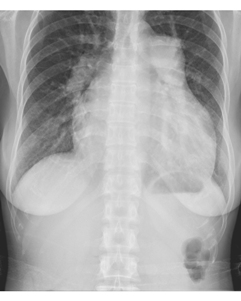

患者,女,33歲。心悸、氣短,活動后明顯。聽診胸骨左緣2~3肋間聞及收縮期雜音,肺動脈第二音亢進。胸部X線平片檢查如下圖: